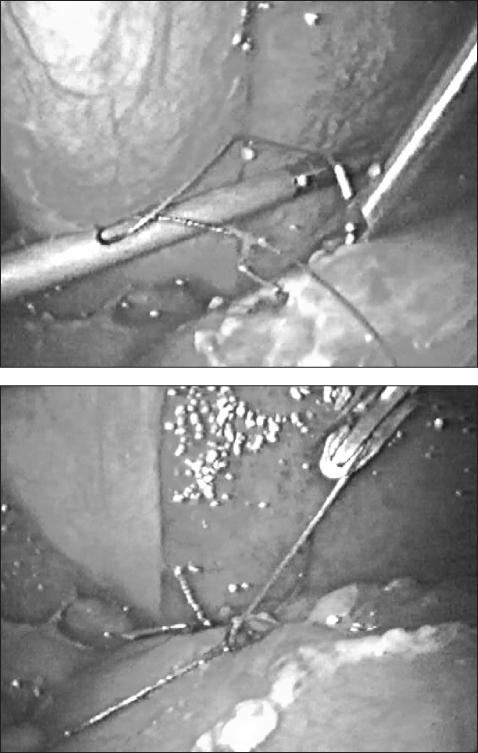

A 75-year-old woman affected by cirrhosis of the liver (Child class C) and chronic gastric ulcer presented with acute abdominal pain. The diagnosis of perforation was made with plain films of the abdomen and computed tomography. Diagnostic laparoscopy showed intense peritonitis due to a perforated ulcer of the anterior gastric wall, 2 cm proximal to the pylorus. Suture closure and placement of an omental patch were performed laparoscopically.

一名75岁患有肝硬化(Child C级)和慢性胃溃疡的女性出现急性腹痛。通过腹部平片和计算机断层扫描做出穿孔诊断。诊断性腹腔镜检查显示,幽门近端2厘米处的胃前壁溃疡穿孔导致严重腹膜炎。通过腹腔镜进行缝合关闭和网膜补片放置。